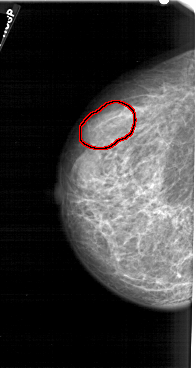

A_1279_1.LEFT_MLO

LEFT_MLO LINES 5176 PIXELS_PER_LINE 2731 BITS_PER_PIXEL 12 RESOLUTION 43.5 OVERLAY

FILE: A_1279_1.LEFT_MLO.OVERLAY

TOTAL_ABNORMALITIES 1

ABNORMALITY 1

LESION_TYPE MASS SHAPE LOBULATED MARGINS CIRCUMSCRIBED

ASSESSMENT 4

SUBTLETY 2

PATHOLOGY BENIGN

TOTAL_OUTLINES 1

BOUNDARY